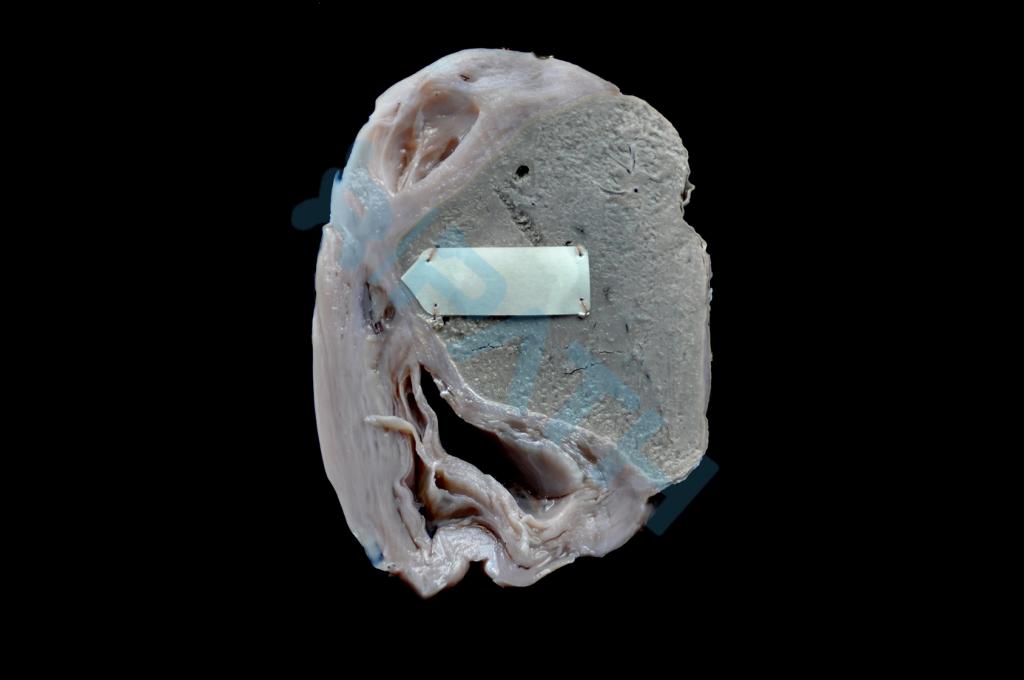

心肌萎缩

肾脏压迫性萎缩

亚急性黄色肝萎缩

子宫肥大(1)

子宫肥大(2)

肝脂肪变性

肾水肿

脾被膜透明变性

(足)干性坏疽

(兔)骨折愈合